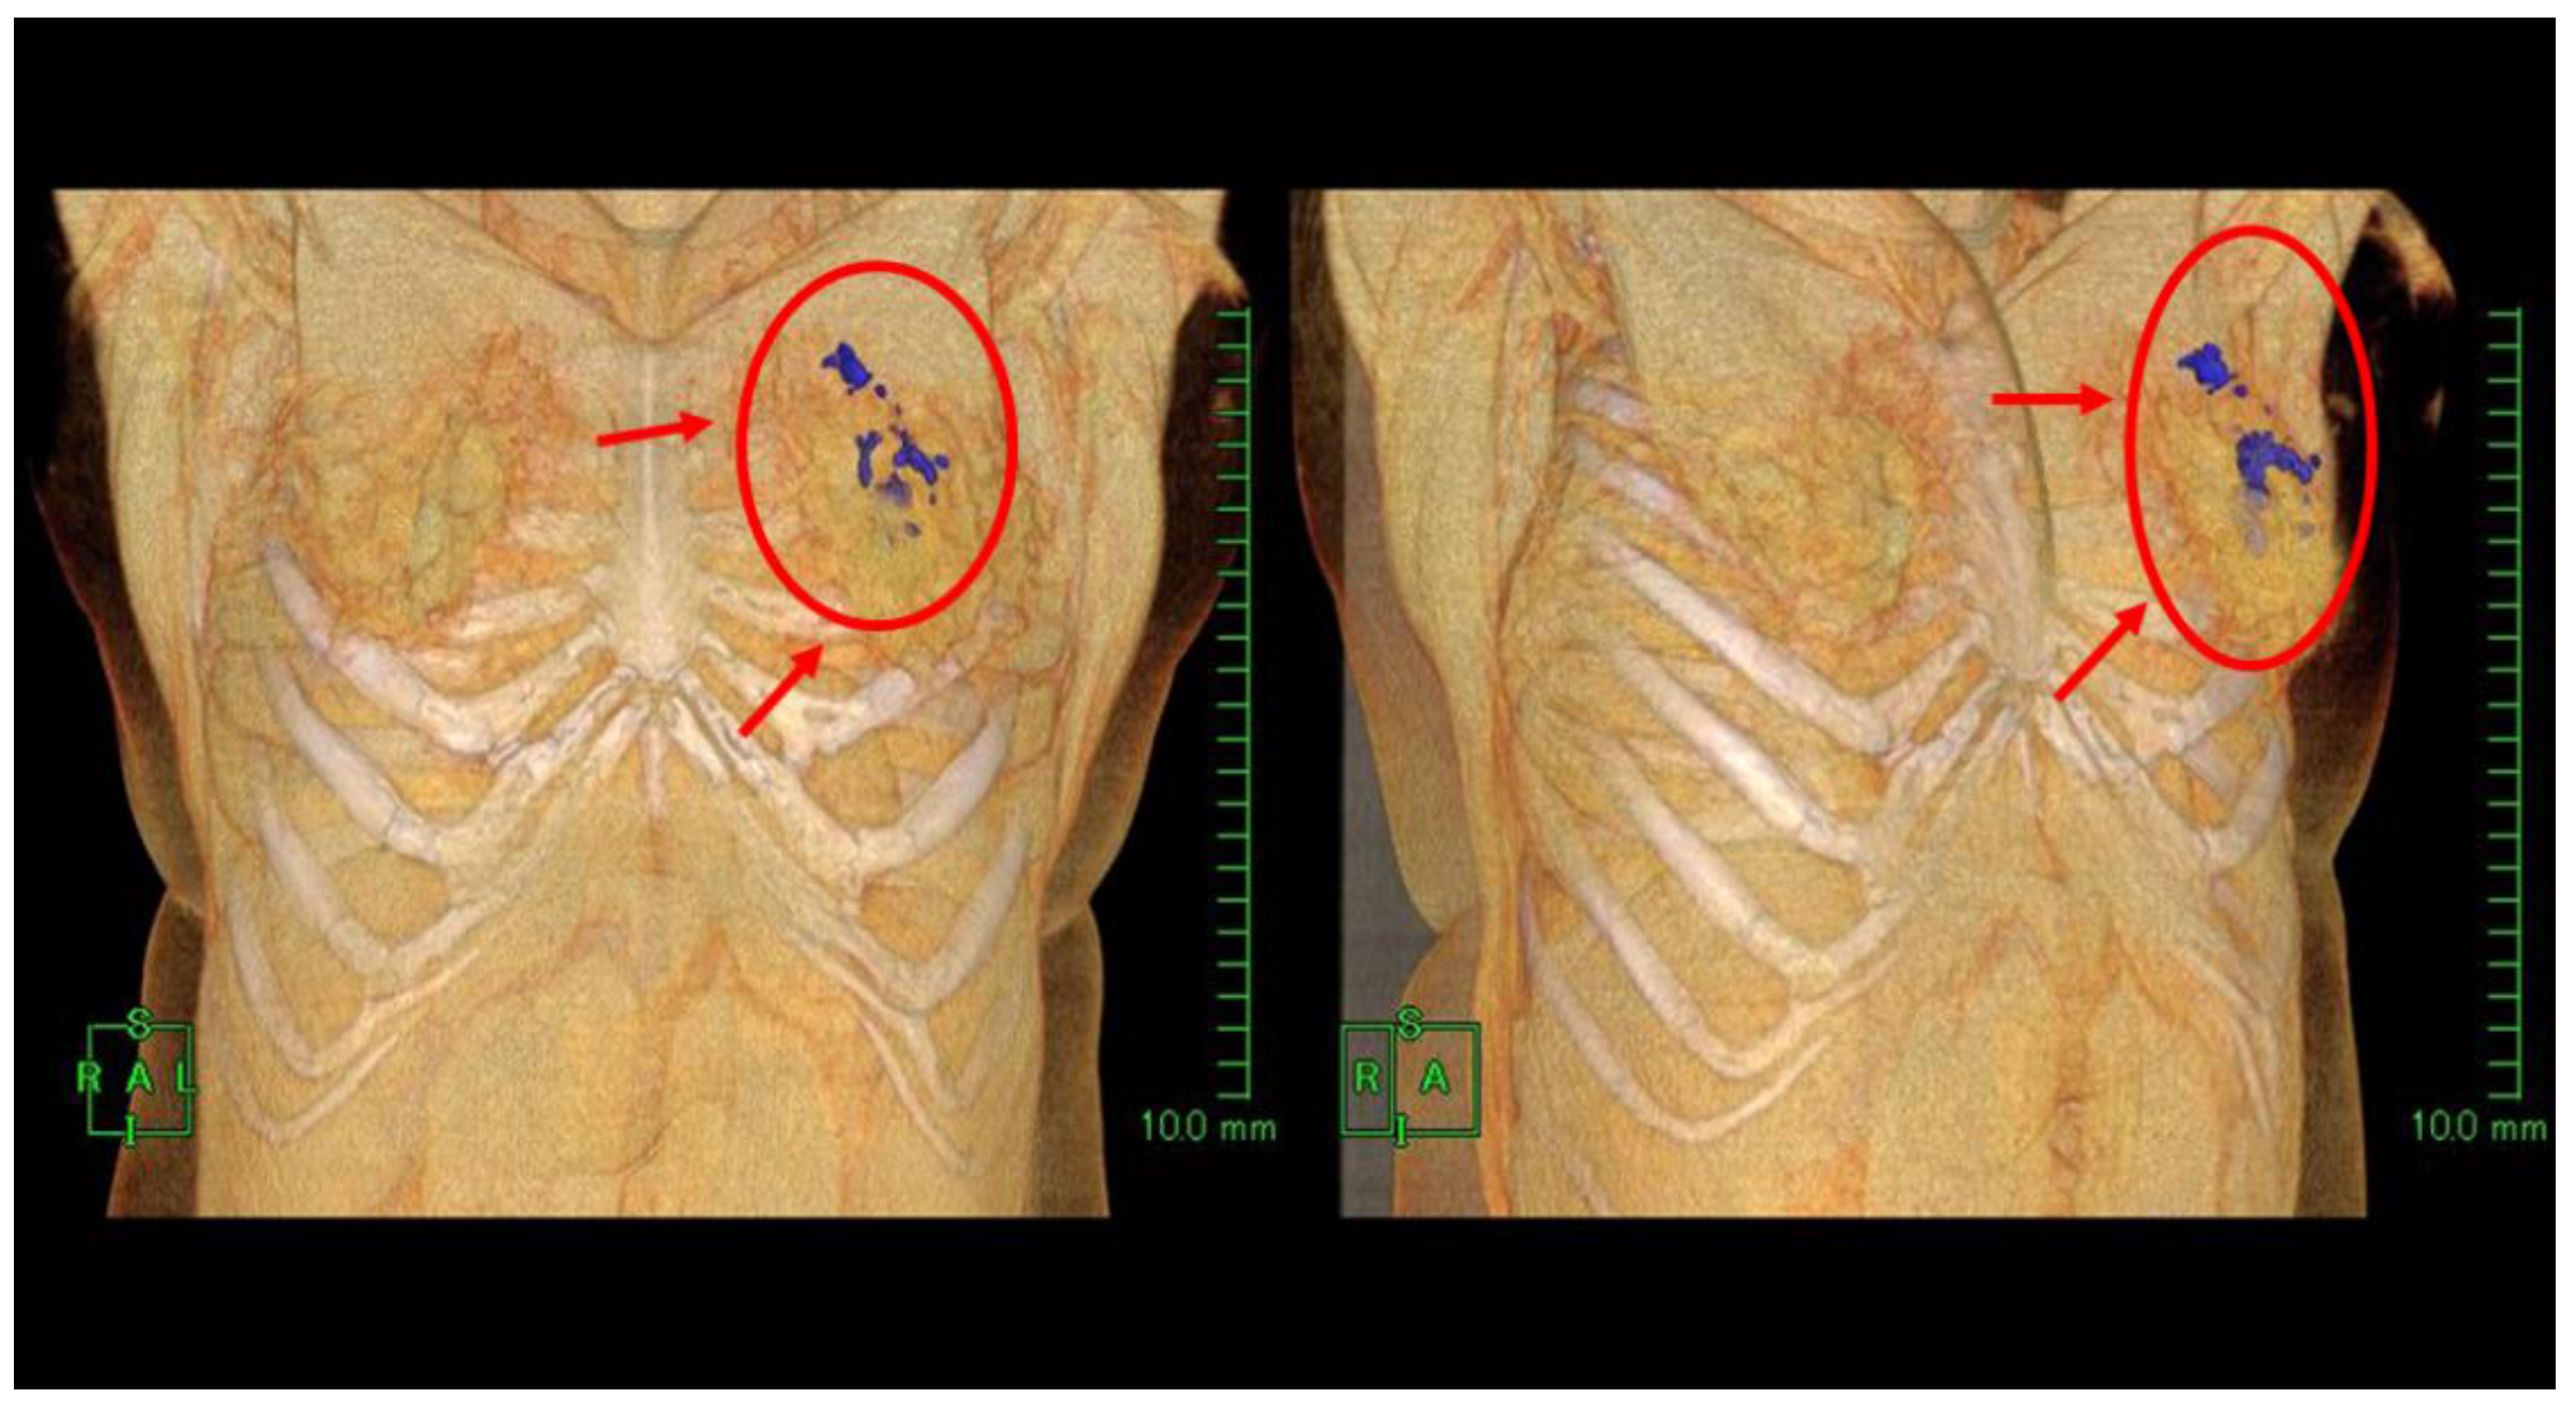

Computed Tomography Demonstration of the Production and Distribution of Oxygen Gas Following Intratumoral Injection of a New Radiosensitizer (KORTUC) for Patients with Breast Cancer—Is Intratumoral Injection Not an Ideal Approach to Solve the Major Problem of Tumor Hypoxia in Radiotherapy?

Hayashi, N.; Ogawa, Y.; Kubota, K.; Okino, K.; Akima, R.; Morita-Tokuhiro, S.; Tsuzuki, A.; Yaogawa, S.; Nishioka, A.; Miyamura, M. Computed Tomography Demonstration of the Production and Distribution of Oxygen Gas Following Intratumoral Injection of a New Radiosensitizer (KORTUC) for Patients with Breast Cancer—Is Intratumoral Injection Not an Ideal Approach to Solve the Major Problem of Tumor Hypoxia in Radiotherapy? Cancers 2016, 8, 43. https://doi.org/10.3390/cancers8040043